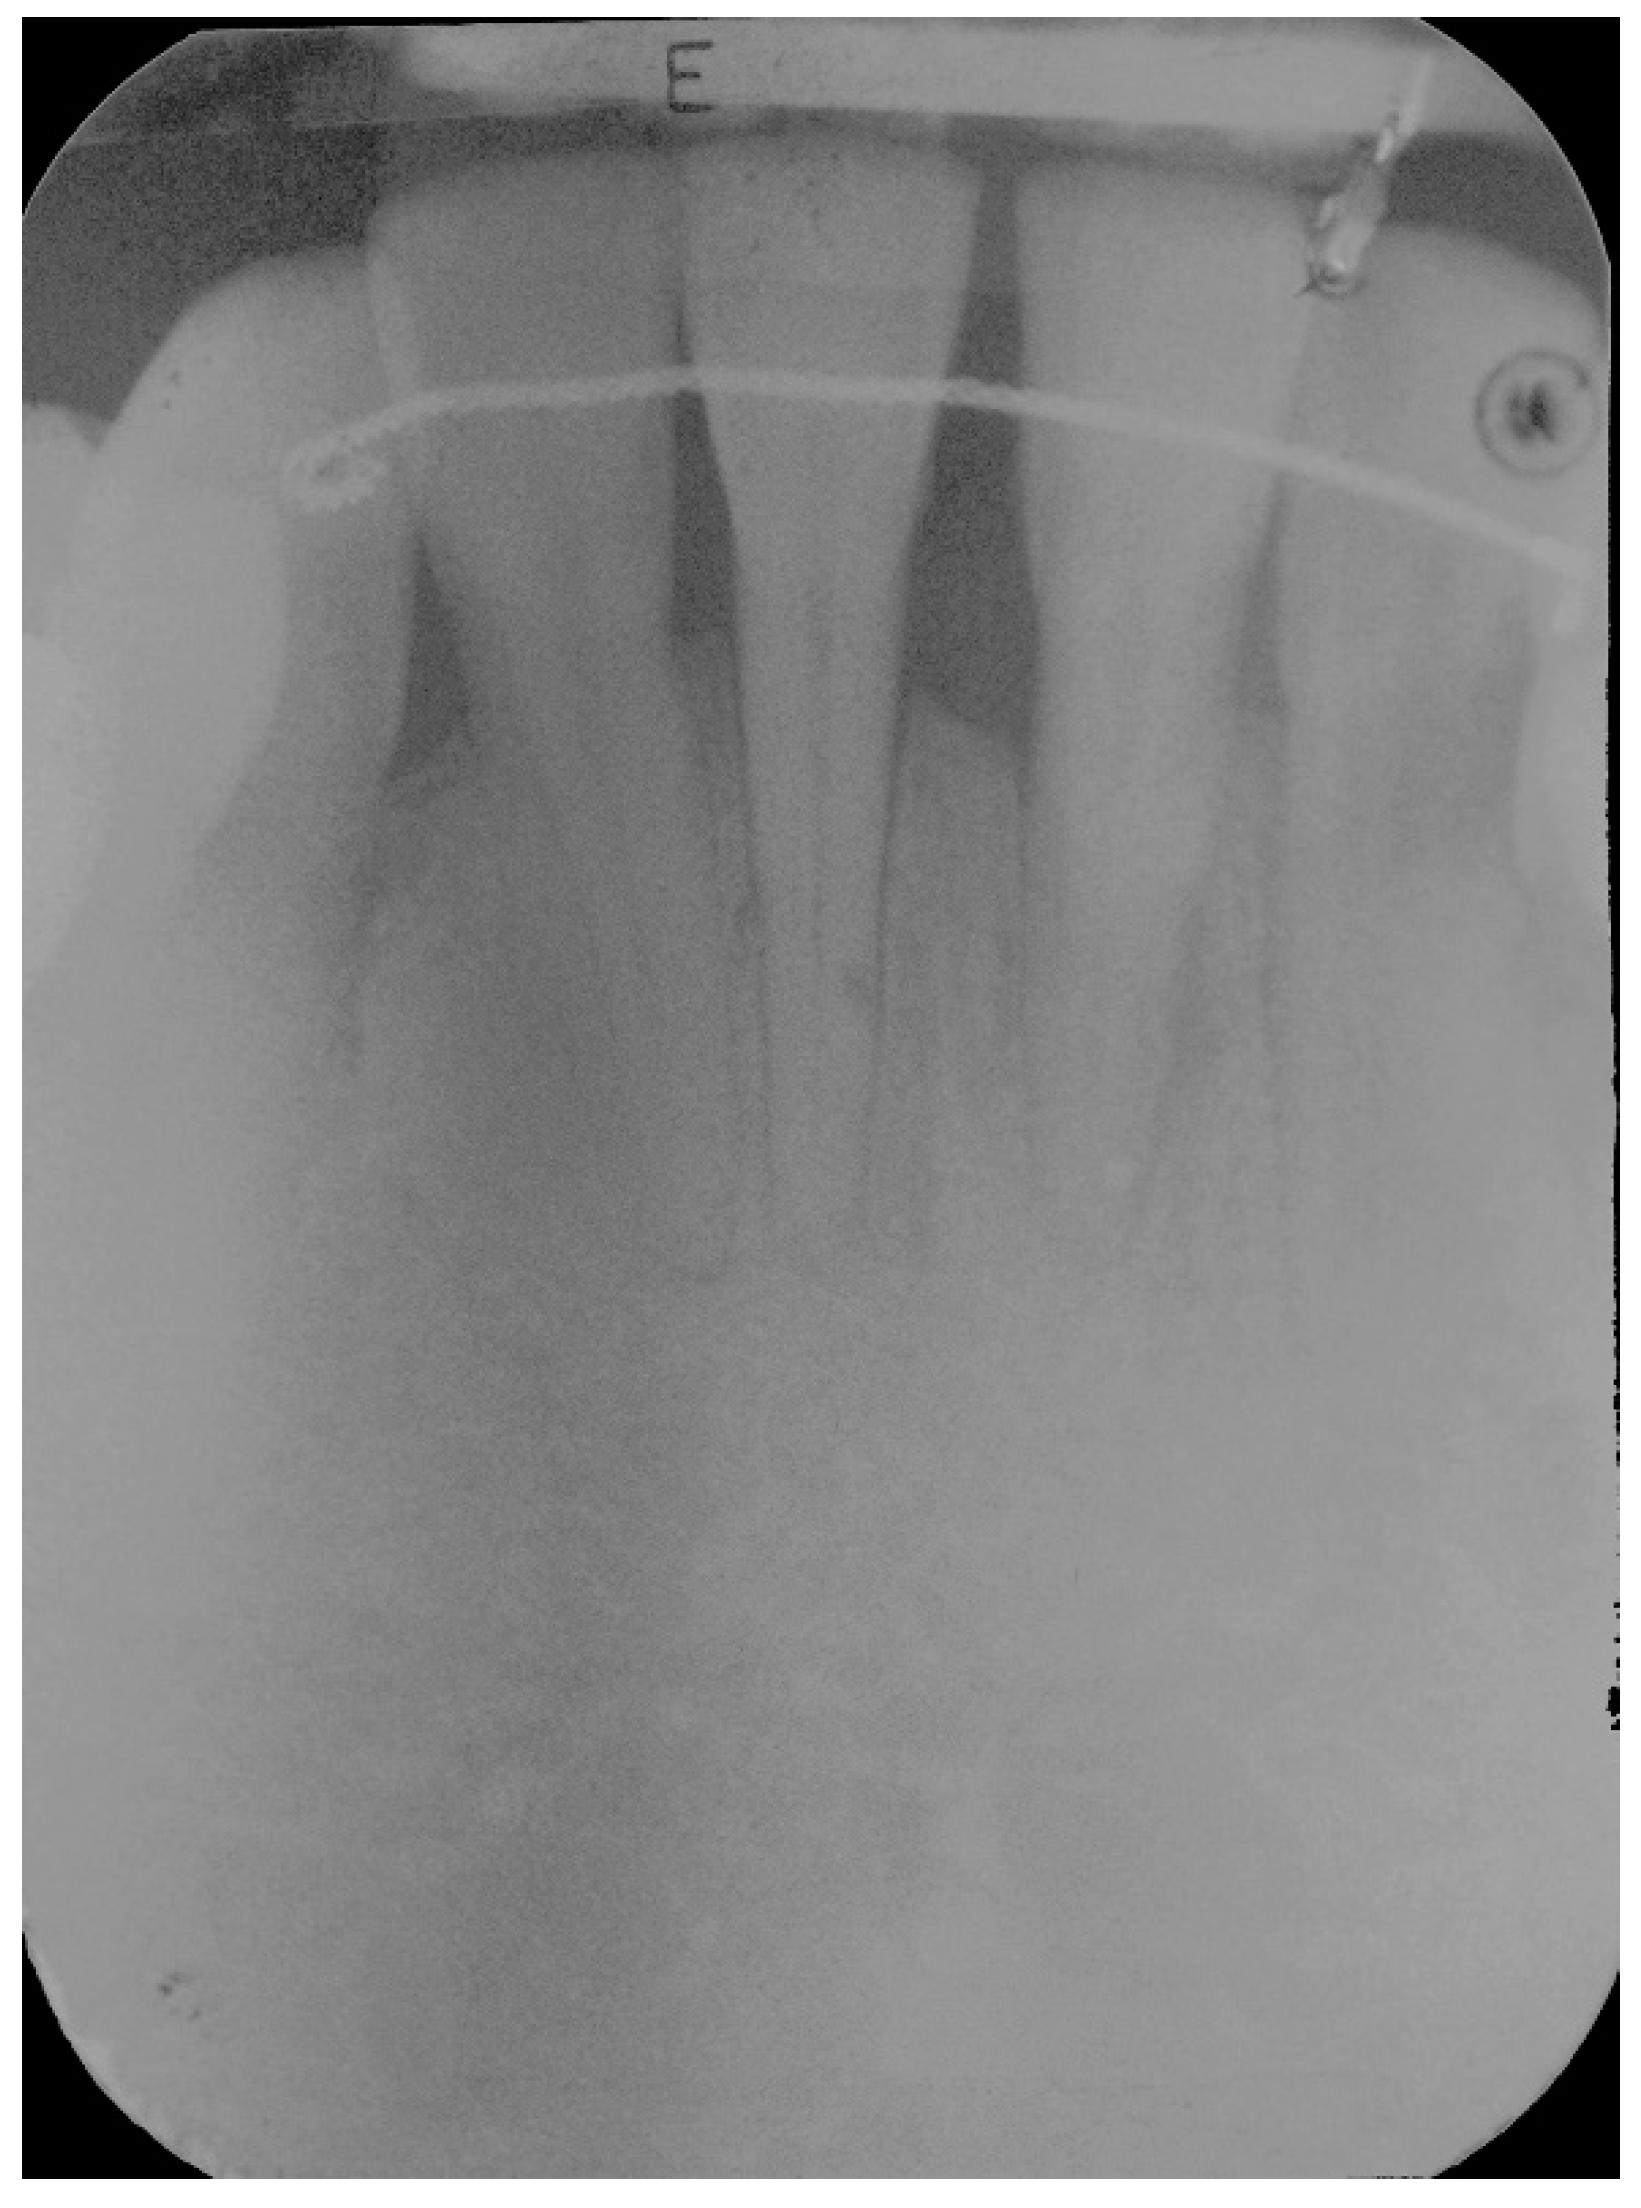

5. Materials and Methods

6. Results